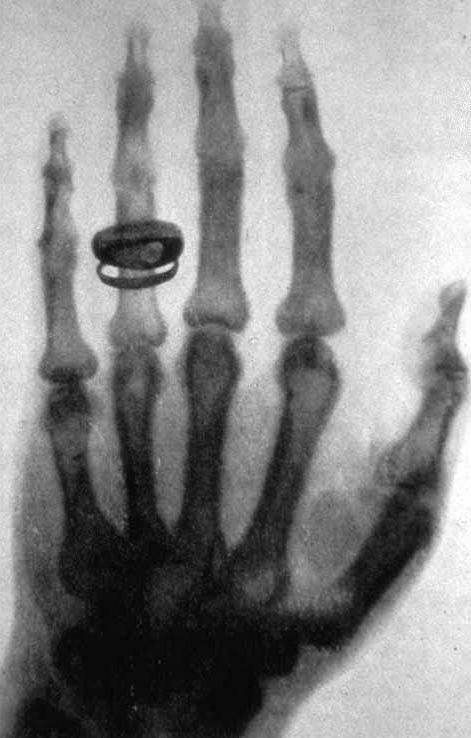

Anna sostenne sempre il marito con grande impegno e con tutte le forze che aveva. Quando Wilhelm trascorse sette settimane isolato nel proprio laboratorio verso la fine del 1895, non solo si prese cura di lui, ma si prestò anche ad essere la prima cavia di quella che sarebbe stata una delle più grandi innovazioni scientifiche. Fu la protagonista della prima radiografia della storia esponendo per 15 minuti la sua mano ai raggi X. Cosa apparve nell’immagine che venne registrata? Le ossa della sua mano sinistra con tanto di anello nuziale sull’anulare. Sconvolta per aver visto le proprie ossa mentre era ancora in vita, Anna non mise mai più piede nel laboratorio di suo marito.

Mentre era intento a studiare il comportamento dei raggi catodici, si accorse che qualcosa di strano stava accadendo. Il foglio di carta su cui era stata scritta la lettera “A” con una soluzione di platinocianuro di bario brillava grazie alla luce emessa dai raggi invisibili provenienti dal tubo a vuoto con cui stava lavorando. Sorpreso e affascinato da quel fenomeno avvicinò la sua mano e lasciò che quel fascio di luce l’attraversasse. L’ombra delle ossa della sua mano appariva adesso sul foglio. Come fermare quel magico istante nel tempo? Röntgen ebbe una geniale intuizione: sostituire il foglio bianco con una lastra fotografica. Adesso era in grado di vedere com’erano gli oggetti al loro interno senza romperli e di conservare quelle immagini nel tempo. Non sapeva bene di cosa si trattasse e proprio per questo li definì raggi X, ma era sicuro si trattasse di qualcosa di straordinario e profondamente innovativo. Era la notte dell’8 novembre 1895.